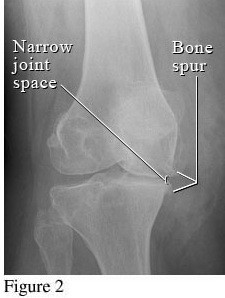

Hình ảnh so sánh giữa khớp bình thường và khớp bị thoái hóa khớp gối

Để phân biệt các giai đoạn của bệnh thoái hóa khớp gối, cần dựa vào phim X- quang theo tiêu chuẩn chẩn đoán thoái hoá khớp của Kellgren và Lawrence như sau:

2. Giai đoạn 2: Thoái hóa khớp gối độ 2

Hình ảnh của khớp gối trên phim X-quang: Khe khớp hẹp nhẹ, có gai xương nhỏ.

Giai đoạn 2 vẫn được xem là giai đoạn tiến triển nhẹ, xem trên phim X-quang có thể thấy kích thước bề mặt sụn khớp vẫn chưa có sự thay đổi nhiều. Bao hoạt dịch khớp vẫn hoạt động bình thường, cung cấp đủ dịch khớp để nuôi dưỡng sụn và bôi trơn ổ khớp, giúp các đầu xương hoạt động được trơn tru. Mặc dù vậy, bệnh nhân vẫn có thể xuất hiện một số triệu chứng như đau mỏi ở khớp gối sau khi vận động nhiều hoặc khi làm việc quá sức, làm việc sai tư thế; cứng khớp khi trời lạnh hoặc do ít vận động khớp.

3. Giai đoạn 3: Thoái hóa khớp gối độ 3

Hình ảnh của khớp gối trên phim X-quang: Khe khớp hẹp rõ, nhiều gai xương kích thước vừa, đặc xương dưới sụn, đầu xương có thể bị biến dạng.

Thoái hóa khớp gối tiến triển đến giai đoạn 3 thì bệnh nhân sẽ càng cảm nhận rõ những cơn đau tại khớp gối. Các lớp sụn khớp bao bọc các đầu xương bị bào mòn nhiều và khoảng không gian giữa các đầu xương bị thu hẹp thấy rõ. Khả năng đi bộ của người bệnh giảm, đi, đứng, ngồi xổm, lên xuống cầu thang cũng thấy đau. Tình trạng cứng khớp vào buổi sáng cũng xảy ra thường xuyên hơn kèm theo các đợt viêm khớp gối (sưng, đau, tràn dịch) hoặc có biểu hiện vẹo khớp gối.